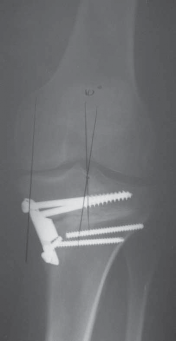

B.

Intraoperative final AP radiograph.

C,D.

Postoperative AP and lateral radiographs.